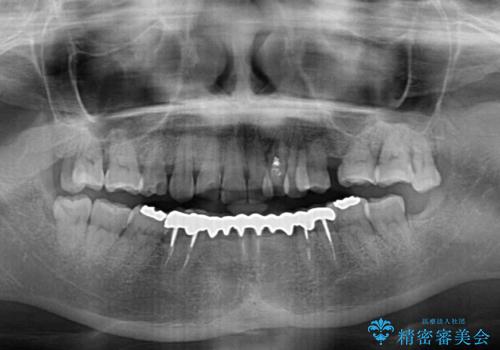

- 常に外れている下顎のブリッジと、前歯のデコボコと色を気にして来院された患者様です。

前歯のデコボコおよび奥歯の咬み合わせを改善するために、上顎左右の小臼歯を欠損スペースを利用して歯列を整え、矯正治療後に気になる上下前歯などをオールセラミッククラウンで美しく仕上げていくこととしました。